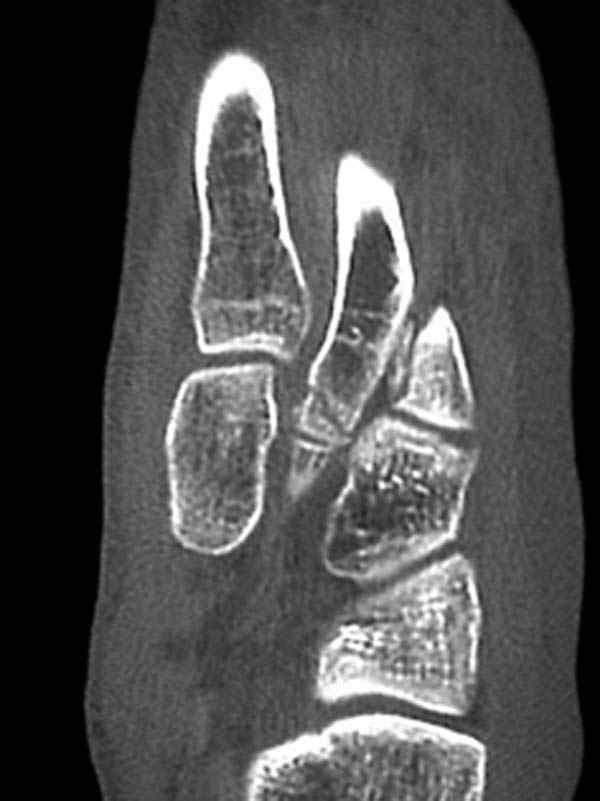

Здесь КТ и сравнительные снимки стопы под нагрузкой.

Диагностировано повреждение медиальной и латеральной колонны.

Если оперативное лечение - как и каким доступом?